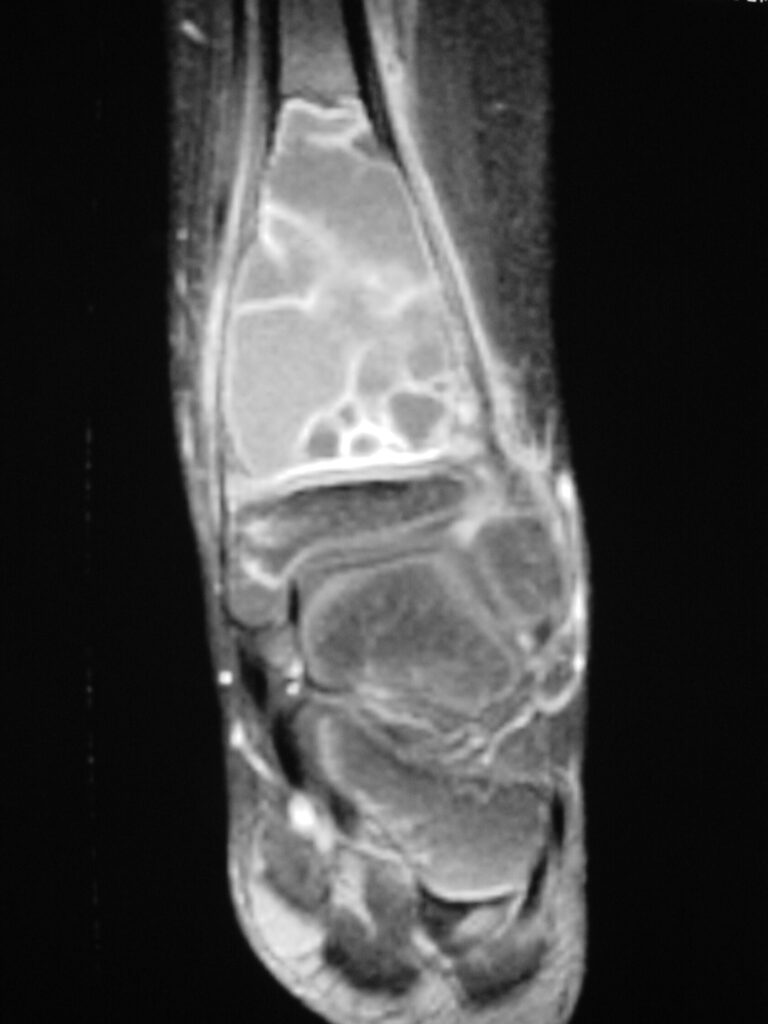

Fig 2 a-e. MRI of an ABC of Distal Tibia: Fig 2 a-c: geographic cystic expansile lesion with fluid-fluid levels. The fluid-fluid levels are caused by bleeding into the cavities. The blood collects and the degredation products settle to the gravity dependent areas of the cavities. This shows up as fluid-fluid levels on the MRI. Fig 2 d,e: This is a gadolinium enhanced MRI of the ABC of the distal tibia. There is peripheral and septal enhancement indication cyst formation. The contrast outlines the cystic cavities but does not enter into the center

Fig 2b: Sagittal T2 weighted MRI of and ABC